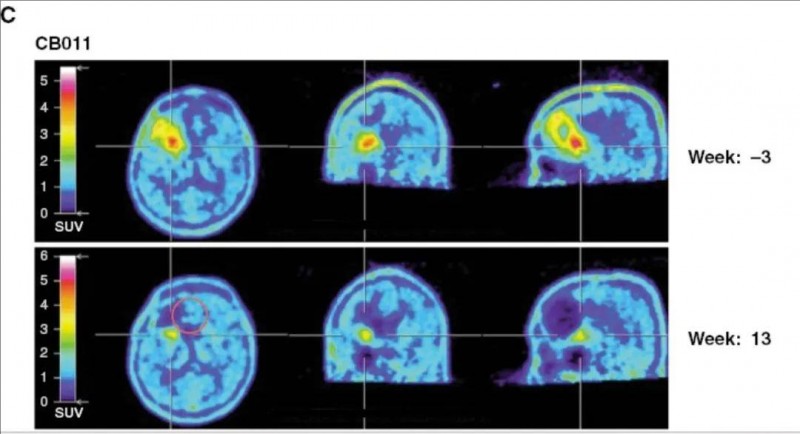

▼患者CB011在局部注射CAR-NK细胞后的18F-FET正电子发射断层扫描

▲图源“Neuro-oncology”,版权归原作者所有,如无意中侵犯了知识产权,请联系我们删除

3、病情稳定:5例患者在CAR-NK治疗后达到病情稳定(SD)。其中,2例患者影像学显示,注射部位出现假进展,提示治疗引起的免疫反应(详见下图)。这两名患者的无进展生存期均为37周,总生存期分别为135周、98周。